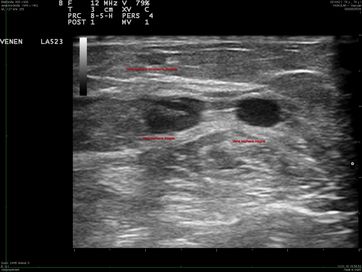

Doppelung der Vena saphena magna in der gleichen Faszienduplikatur

Doppelung der Vena saphena magna in zwei verschiedenen Faszienduplikaturen, zusätzlich dritte subkutane Vena saphena akzessoria medialis

Doppelung mit zwei gleich großen Ästen intrafaszial und subkutan

Doppelung mit variköser Vena saphena akzessoria medialis subkutan und normal weiter Vena saphena magna intrafaszial, beim Valsalva Reflux in beiden Ästen

Doppelung der Vena saphena magna in zwei verschiedenen Faszienlogen

Bei Bauchpresse Reflux nur in einem Ast der doppelten Vsm

Doppelung mit variköser Vena saphena magna intrafaszial und unauffälliger Vena saphena akzessoria medialis subkutan